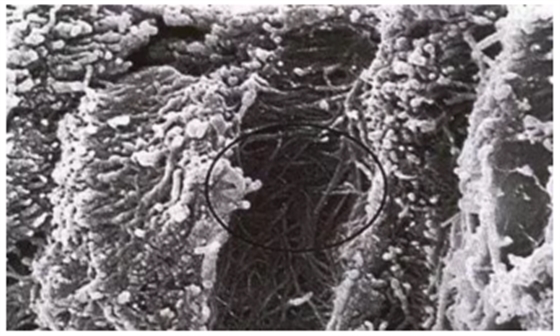

牙本質(zhì)縱斷面。管周牙本質(zhì)被去除,管間牙本質(zhì)膠原纖維暴露(放大倍數(shù)5000)